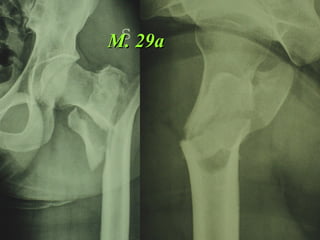

M. 29a

Dal Gennaio 2005 ad Agosto 2006 110  placche di Gotfried Età media  : 78 anni (range 29-94) Tempo chirurgico: 30 minuti (range 12-45) IMMEDIATA CONCESSIONE DEL CARICO